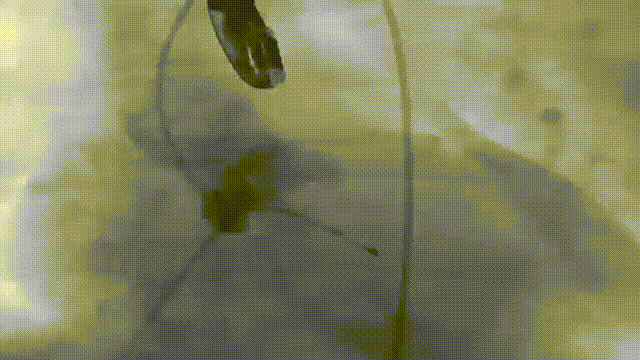

右冠保护

反复造影确认冠脉风险